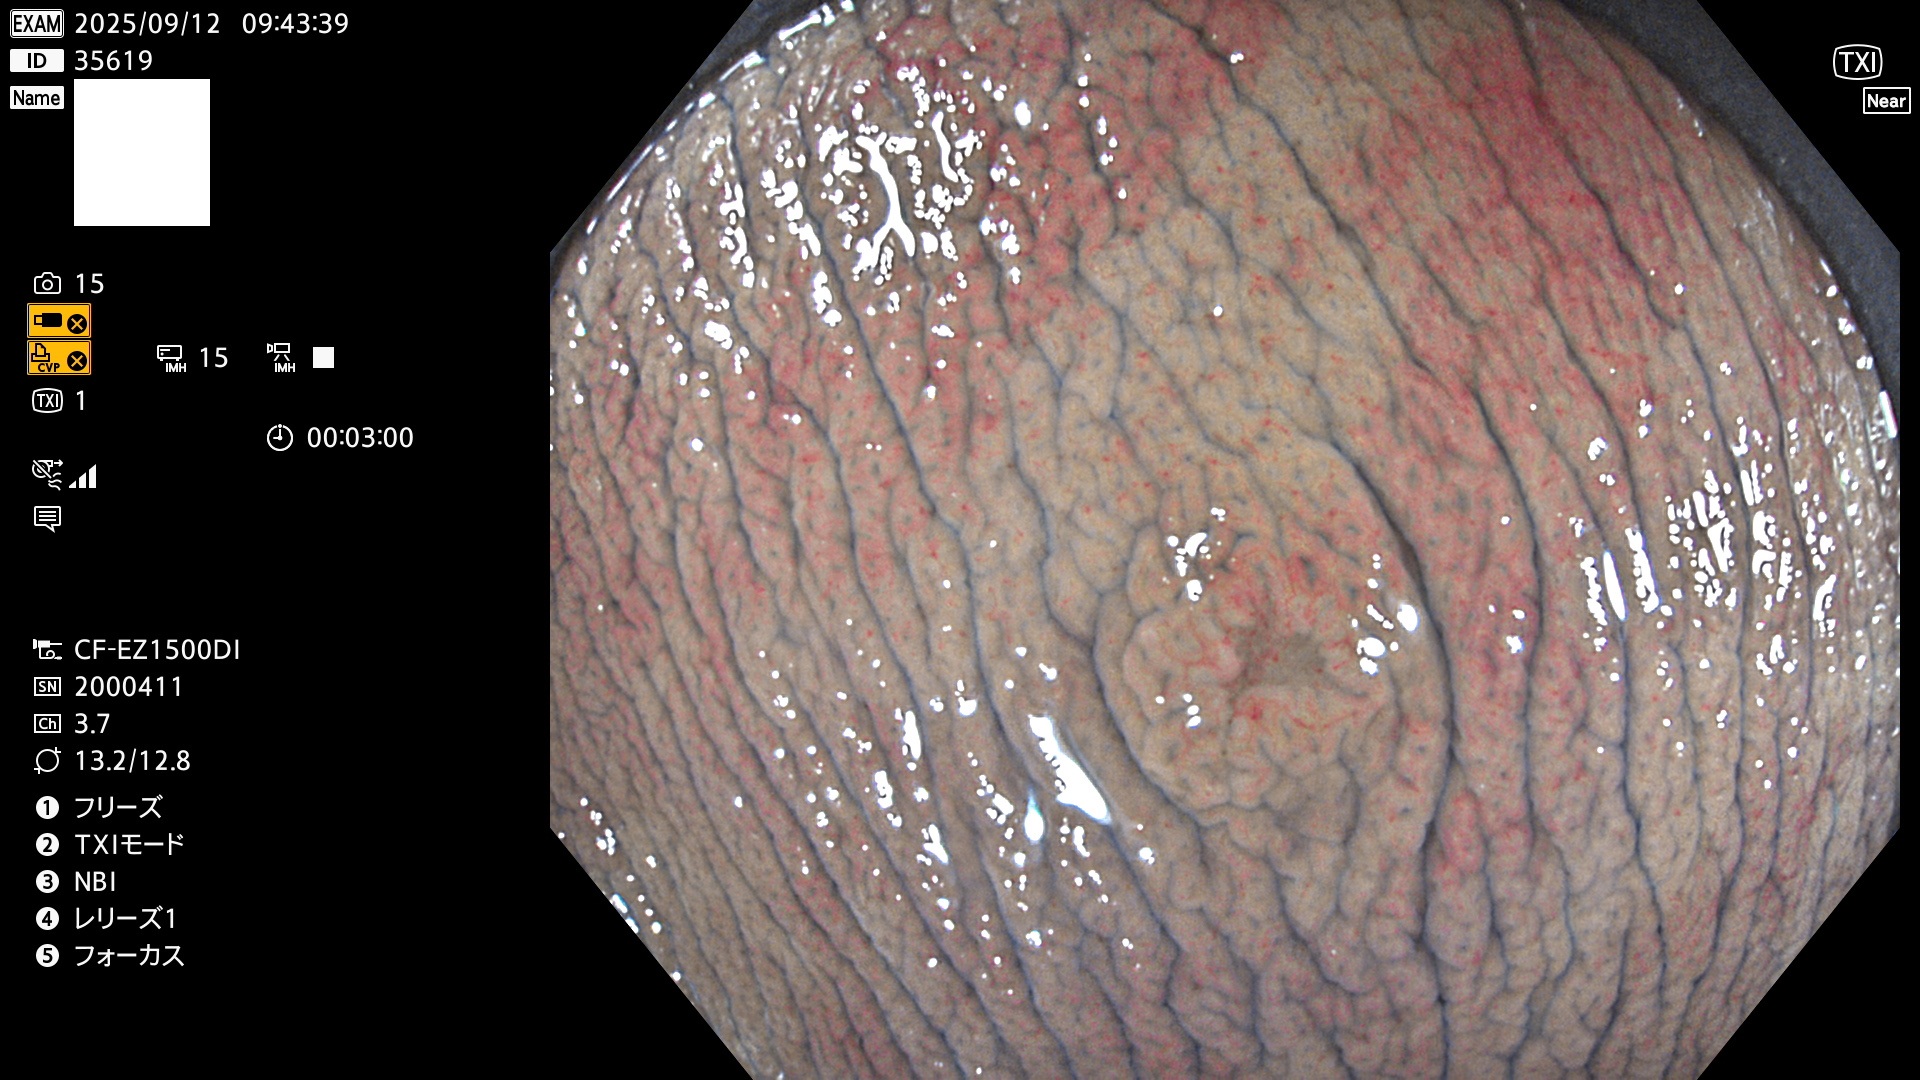

完全に平坦な物をUb、陥凹している物をUcと呼びます。Ubは認識が困難で、Ucはびらん(炎症)と紛らわしいために見落とされやすく、「内視鏡後・大腸癌」の原因になります。

専門的)Uc=De Novo癌? 内視鏡の解像度が低かった時代、このような説もありました。しかし今日の高精度内視鏡では良性の微小なUc型腺腫(APC遺伝子異常の腺腫)が日常的に見つかります。Ucこそが多段階発癌(Adenoma-Carcinoma Sequence)のMain Routeです。

毎週の検査(木・金・土・日)に発見されたUbとUc型・腺腫を、その週の日曜の夜にUPし1週間、提示します。

2025年9月11日〜9月14日の4日間(40件)7個 (Uc_ADR=7個/40人=18%)